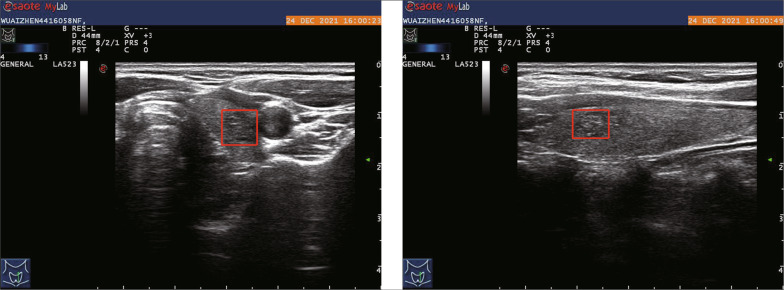

Our dataset, labeled as dataset A, was collected from Panyu Central Hospital in Guangzhou and is crucial for training our deep learning model. The dataset was annotated by experienced physicians at the hospital over a span of one year, using pathological validation as the basis. The labeling process involved identifying thyroid nodules and assigning boundary boxes to them, along with classifying them as benign or malignant. Dataset A comprises a total of 607 patients, with 258 cases labeled as benign and 349 cases labeled as malignant. This results in a total of 1214 images in the dataset. Each patient in the dataset has six ultrasound images captured using Mylab series ultrasound instruments manufactured by Esaote, an Italian company, or ultrasound instruments produced by GE Medical Group. These images include both transverse and longitudinal sections of the thyroid. Additionally, color ultrasound and elastic imaging were performed, but only the thyroid ultrasound data from standard sections were utilized for our study. The images obtained from the instruments are in the form of three-channel BMP images, with resolutions of 600800 and 12801024 pixels. Show as Fig. 8. Among the six images per patient, four of them serve as auxiliary positioning data. These images are accompanied by biopsy results and a marked box indicating the location of the nodules. By utilizing the marked boxes, we can accurately extract the corresponding nodule regions from these images. This portion of the dataset is further divided into five subsets for training and model validation purposes.

Fig. 8.

Self-collected data and its labels